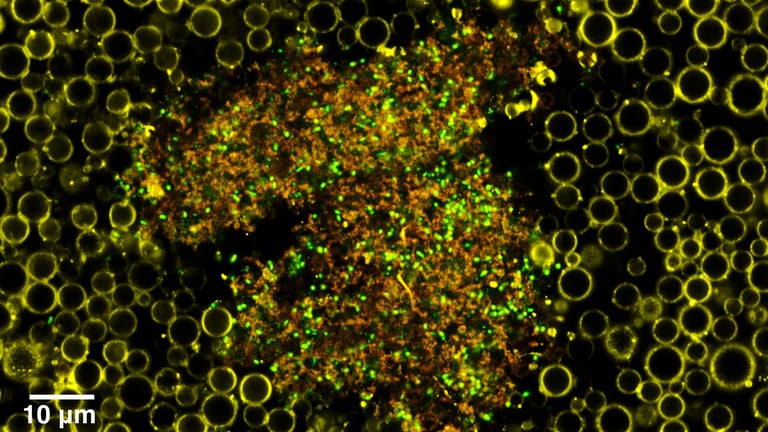

This cutting-edge system utilizes engineered nanoparticles that release antibiotics when activated by ultrasound, allowing for non-invasive disruption of biofilms and targeted treatment of infections.

These biofilms, which are protective matrices formed by bacteria, contribute to antimicrobial resistance by shielding bacteria from immune responses and drugs, potentially increasing resistance by up to 1000-fold.